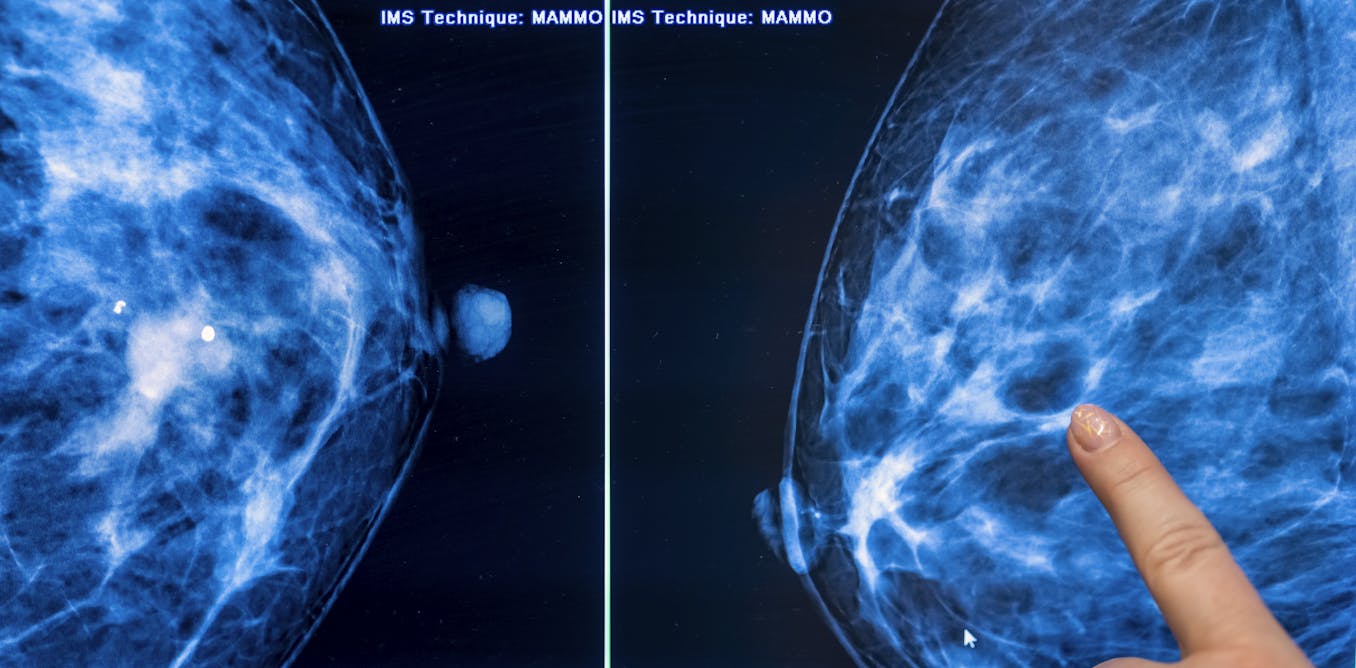

Dense breasts are composed of more fibrous, connective tissue and glandular tissue – meaning glands that produce milk and tubes that carry it to the nipple – than fatty tissue. Because fibroglandular tissue and breast masses both look white on mammographic images, greater breast density makes it more difficult to detect cancer. Nearly half of all American women are categorized as having dense breasts.

Standard mammograms use X-rays to produce two-dimensional images of the breast. A newer type of mammography imaging called tomosynthesis produces 3D images, which find more cancers among women with dense breasts. So, researchers and doctors generally agree that women with dense breasts should undergo tomosynthesis screening when available.